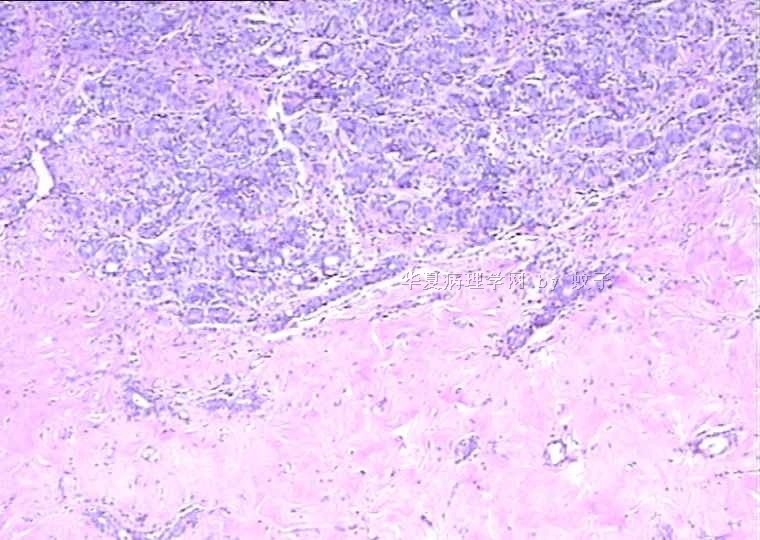

B2156乳腺活检

姓    名: ××× 性别:  女 年龄:  20

简要病史:  右乳包块8年。

肉眼检查:  灰白不整形组织一块,切面灰白,灰红,实性,质韧。

• 乳腺活检图3

图3

标签:乳腺腺病

有包膜吗?良性,首先考虑纤维腺瘤(图5、6透明变的纤维支持),其次腺瘤。

无明显包膜,界限较清,

我们考虑腺瘤,(图5,6为混有纤维瘤组织)

腺病瘤(主要成份旺炽性腺病)部分区域为纤维腺瘤(管内型)